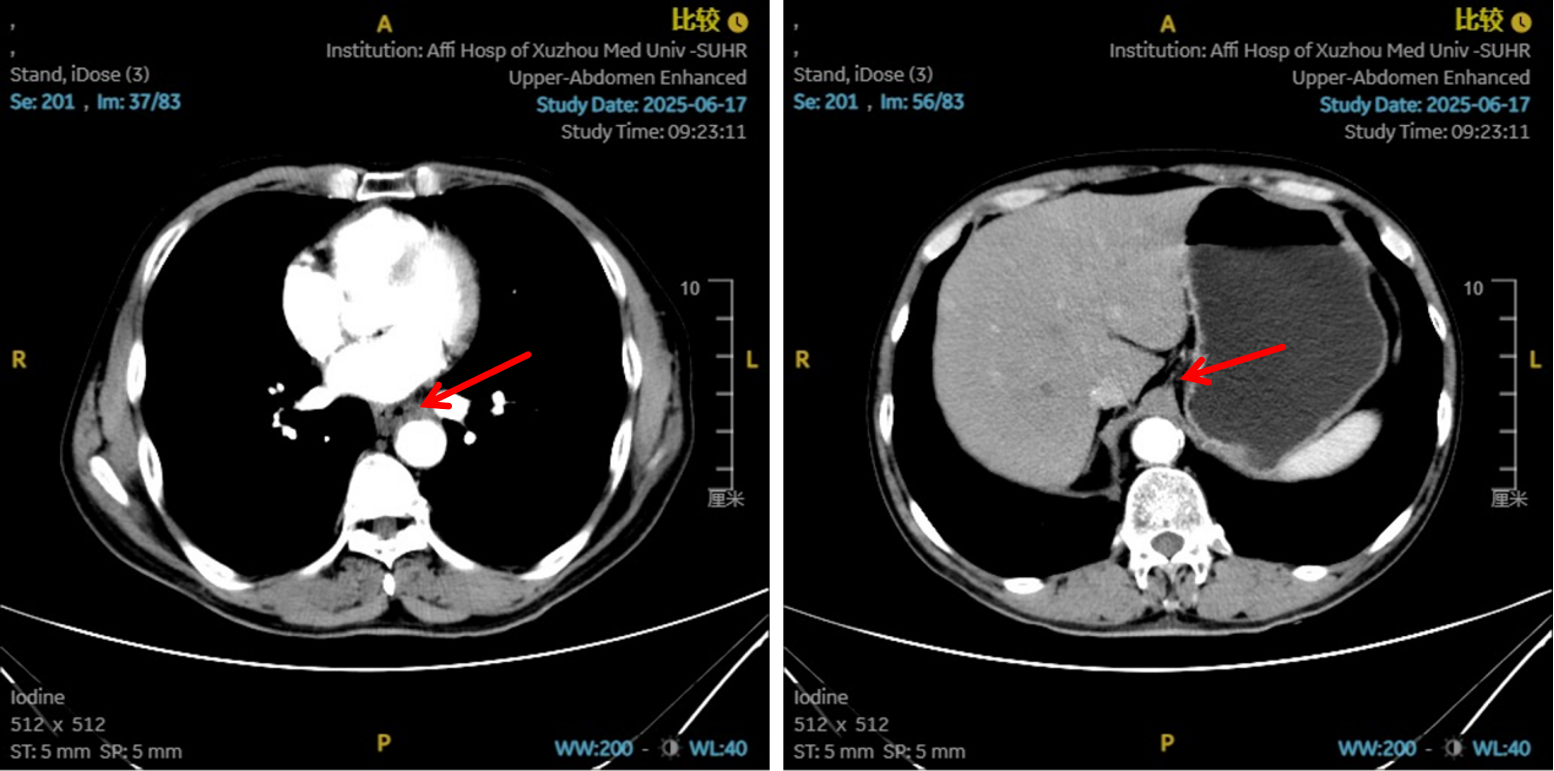

2. 巩固与协同治疗(第3-6周期):

方案:在原有方案基础上联合PD-1抑制剂(紫杉醇聚合物胶束300mg+洛铂40mg+重组人血管内皮抑制素210mg+信迪利单抗200mg)。在化疗造成肿瘤细胞大量死亡、释放抗原的同时,联合PD-1抑制剂,解除T细胞抑制,激活全身性、长效的抗肿瘤免疫应答。

图5:4、6周期化免靶后食管癌病灶对比

图6:4、6周期化免靶后淋巴结对比

图7:4周期治疗后影像学 [图左:“食管Ca化疗后”,食管胸中下段管壁增厚,较厚处管壁约12mm,边缘模糊,病灶局部与邻近大血管、气管壁分界不清。图右:纵隔内(3P、4、7)、左肺门示稍大淋巴结影。]

图8:6周期治疗后影像学 [图左:“食管Ca化疗后”,食管胸中下段管壁增厚,较厚处管壁约10mm,边缘模糊,病灶局部与邻近大血管、气管壁分界不清。图右:纵隔内(3P、4、7)示小淋巴结影。]

疗效评估

治疗2周期后,食管壁厚度由17mm降至15mm,淋巴结由18mm×15mm缩小至16mm×13mm;4周期后,食管壁进一步缩至12mm,淋巴结明显减少;6周期后,食管壁仅余10mm,纵隔内仅见小淋巴结影,疗效评估“接近CR”。